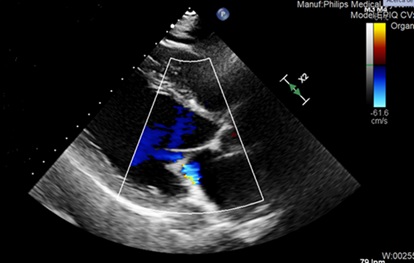

Ante sospecha de miocardiopatía dilatada, se realiza ecocardiograma que pone de manifiesto dilatación severa del ventrículo izquierdo con hipocinesia global severa y FEVI 32%, acompañado de ligera dilatación auricular izquierda e insuficiencia mitral funcional moderada con ligero derrame pericárdico.